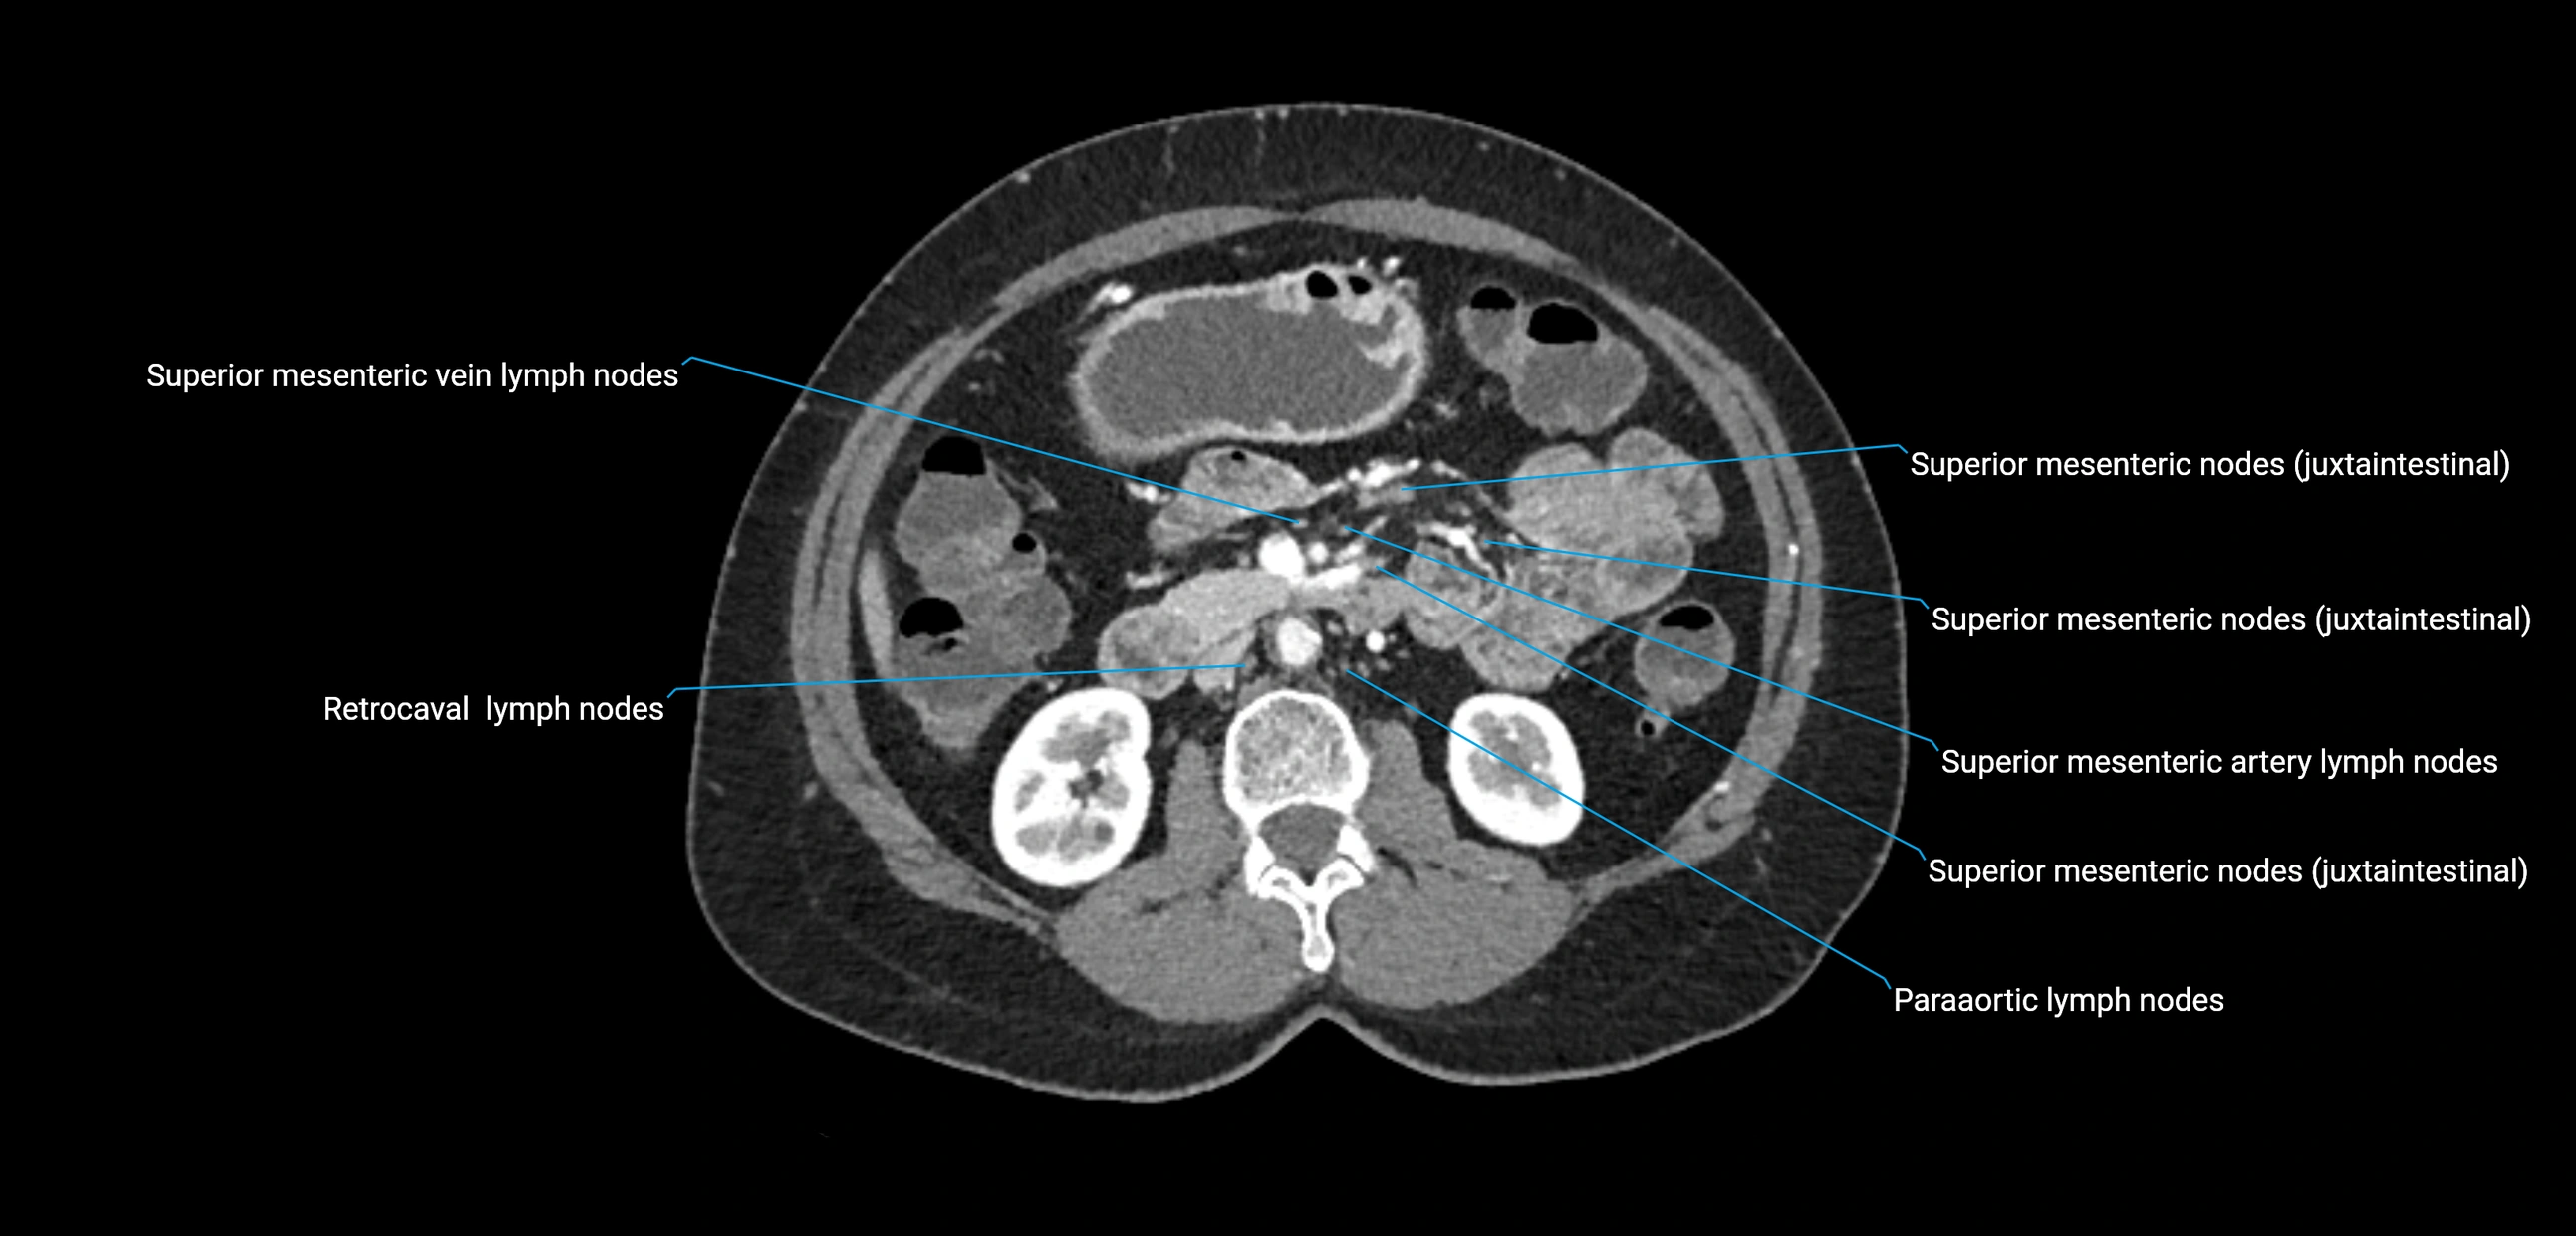

CT Appearance

CT Pre-Contrast:

• Nodes appear as soft-tissue density nodules adjacent to the aorta and IVC

• Calcification may be seen in chronic infections (e.g., tuberculosis)

CT Post-Contrast:

• Normal nodes enhance homogeneously

• Malignant nodes may show heterogeneous enhancement, central necrosis, or conglomerate formation

• Size >1 cm short axis is suspicious, though morphology and distribution are equally important